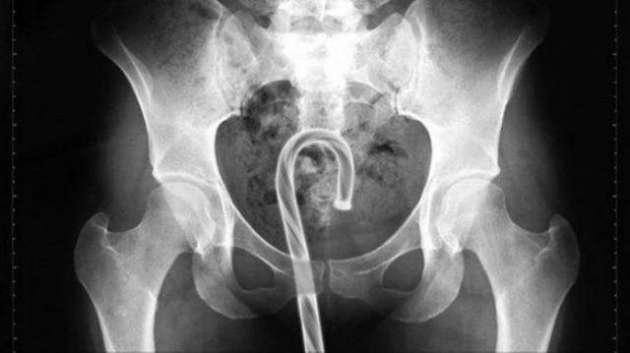

İÇİNDEKİ ŞEYE RÖNTGEN UZMANLARI ŞOK OLDU!

RÖNTGEN UZMANLARI ŞOK OLDU!

,Dünyada çekilen bu röntgenler hem röntgen uzmanlarını hemde görenleri şok ediyor...